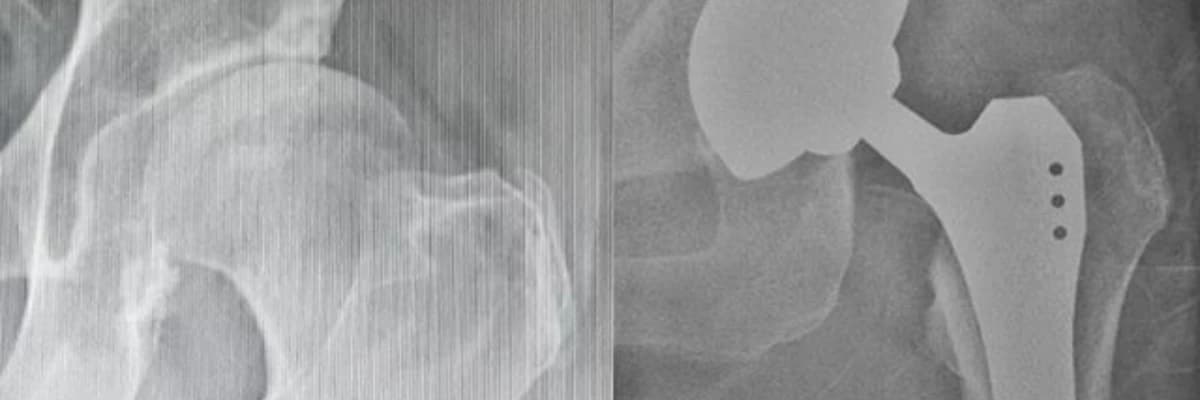

KALÇA KİREÇLENMESİ VE TOTAL KALÇA PROTEZİ

Kalça eklemindeki kıkırdak yapısının harabiyetine kalça kireçlenmesi denir. Diğer tedavilere rağmen yaşamsal aktiviteleri ileri derecede kısıtlanmış, ağrısız yol yürüme mesafeleri azalmış 60-80 yaş arası hastalar cerrahi tedavi için ideal hasta grubunu oluştururlar. Romatoid artrit, kalça ekleminde osteonekroz gibi durumlarda daha genç yaştaki hastalara da protez ameliyatları yapılabilir. Cerrahi tedavide hasarlı eklem çıkartılarak yerine metal, seramik, polietienden ( yüksek dirençli bir plastik türevi) oluşan parçalar kullanılarak yapay ağrısız ve fonksiyonel bir kalça eklemi oluşturulur.